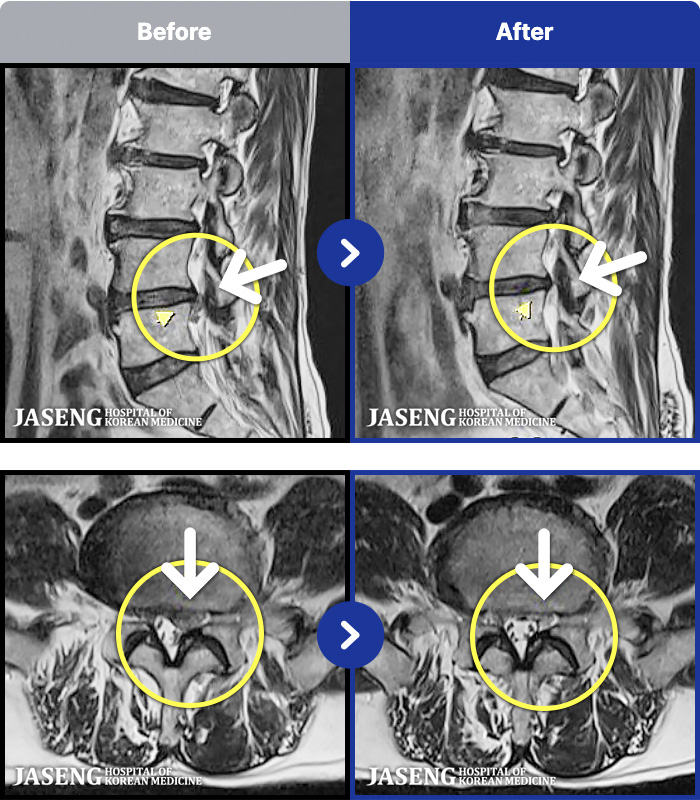

MRI ġ

1,240 MRI ũ ʸ Ȯϼ.

[_㸮ũ] 㸮 ϰ , ̾ ϼ̽ϴ.

[ϻ_㸮ũ] ϰ ӵǾϴ. ߰ Ͽ ߰ Ǵ ߵ ̻ ȣϴ ¿ϴ.

[λ_㸮ũ] 㸮 㸮 ̸ ִ.

[Ȼ_㸮ũ] 㸮 ְ ٸ ȱⰡ .

[_㸮ũ] 㸮 , ٸ ̾ ϼ̽ϴ.

[õ_㸮ũ] ߲ 㸮 , ٷ

[ϻ_㸮ũ] ݺ ӵǸ ڼ ÿ ȭǴ ߵ ̻ ȣϴ ¿ϴ.

[ϻ_㸮ũ] ؽϰ ߰ ̴ · ϻȰ ¿ϴ.

[ؿ_㸮ũ] 㸮 ϰ